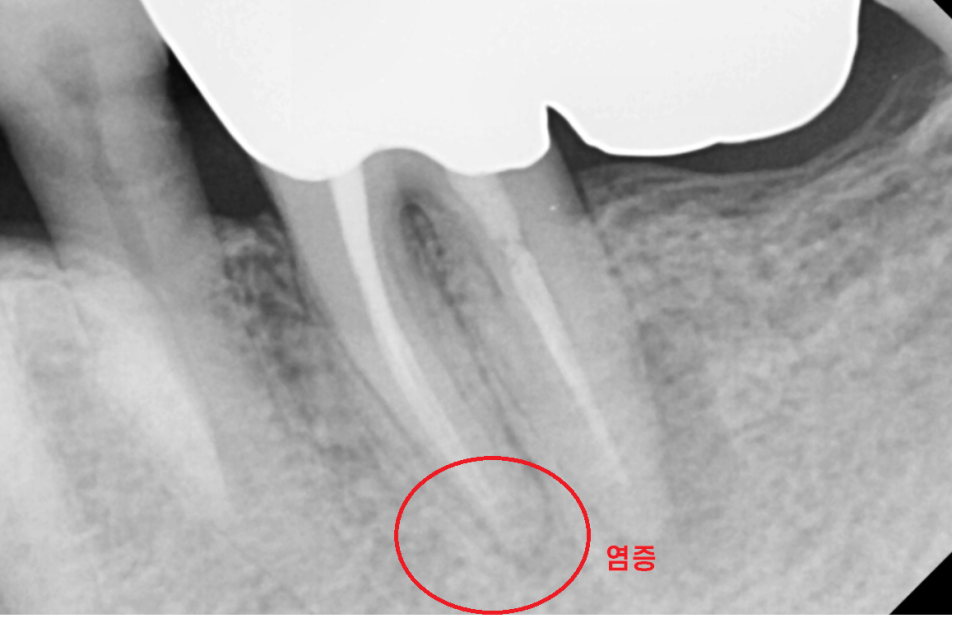

23.06.27

역시나 뿌리 끝에 염증이 보이네요.